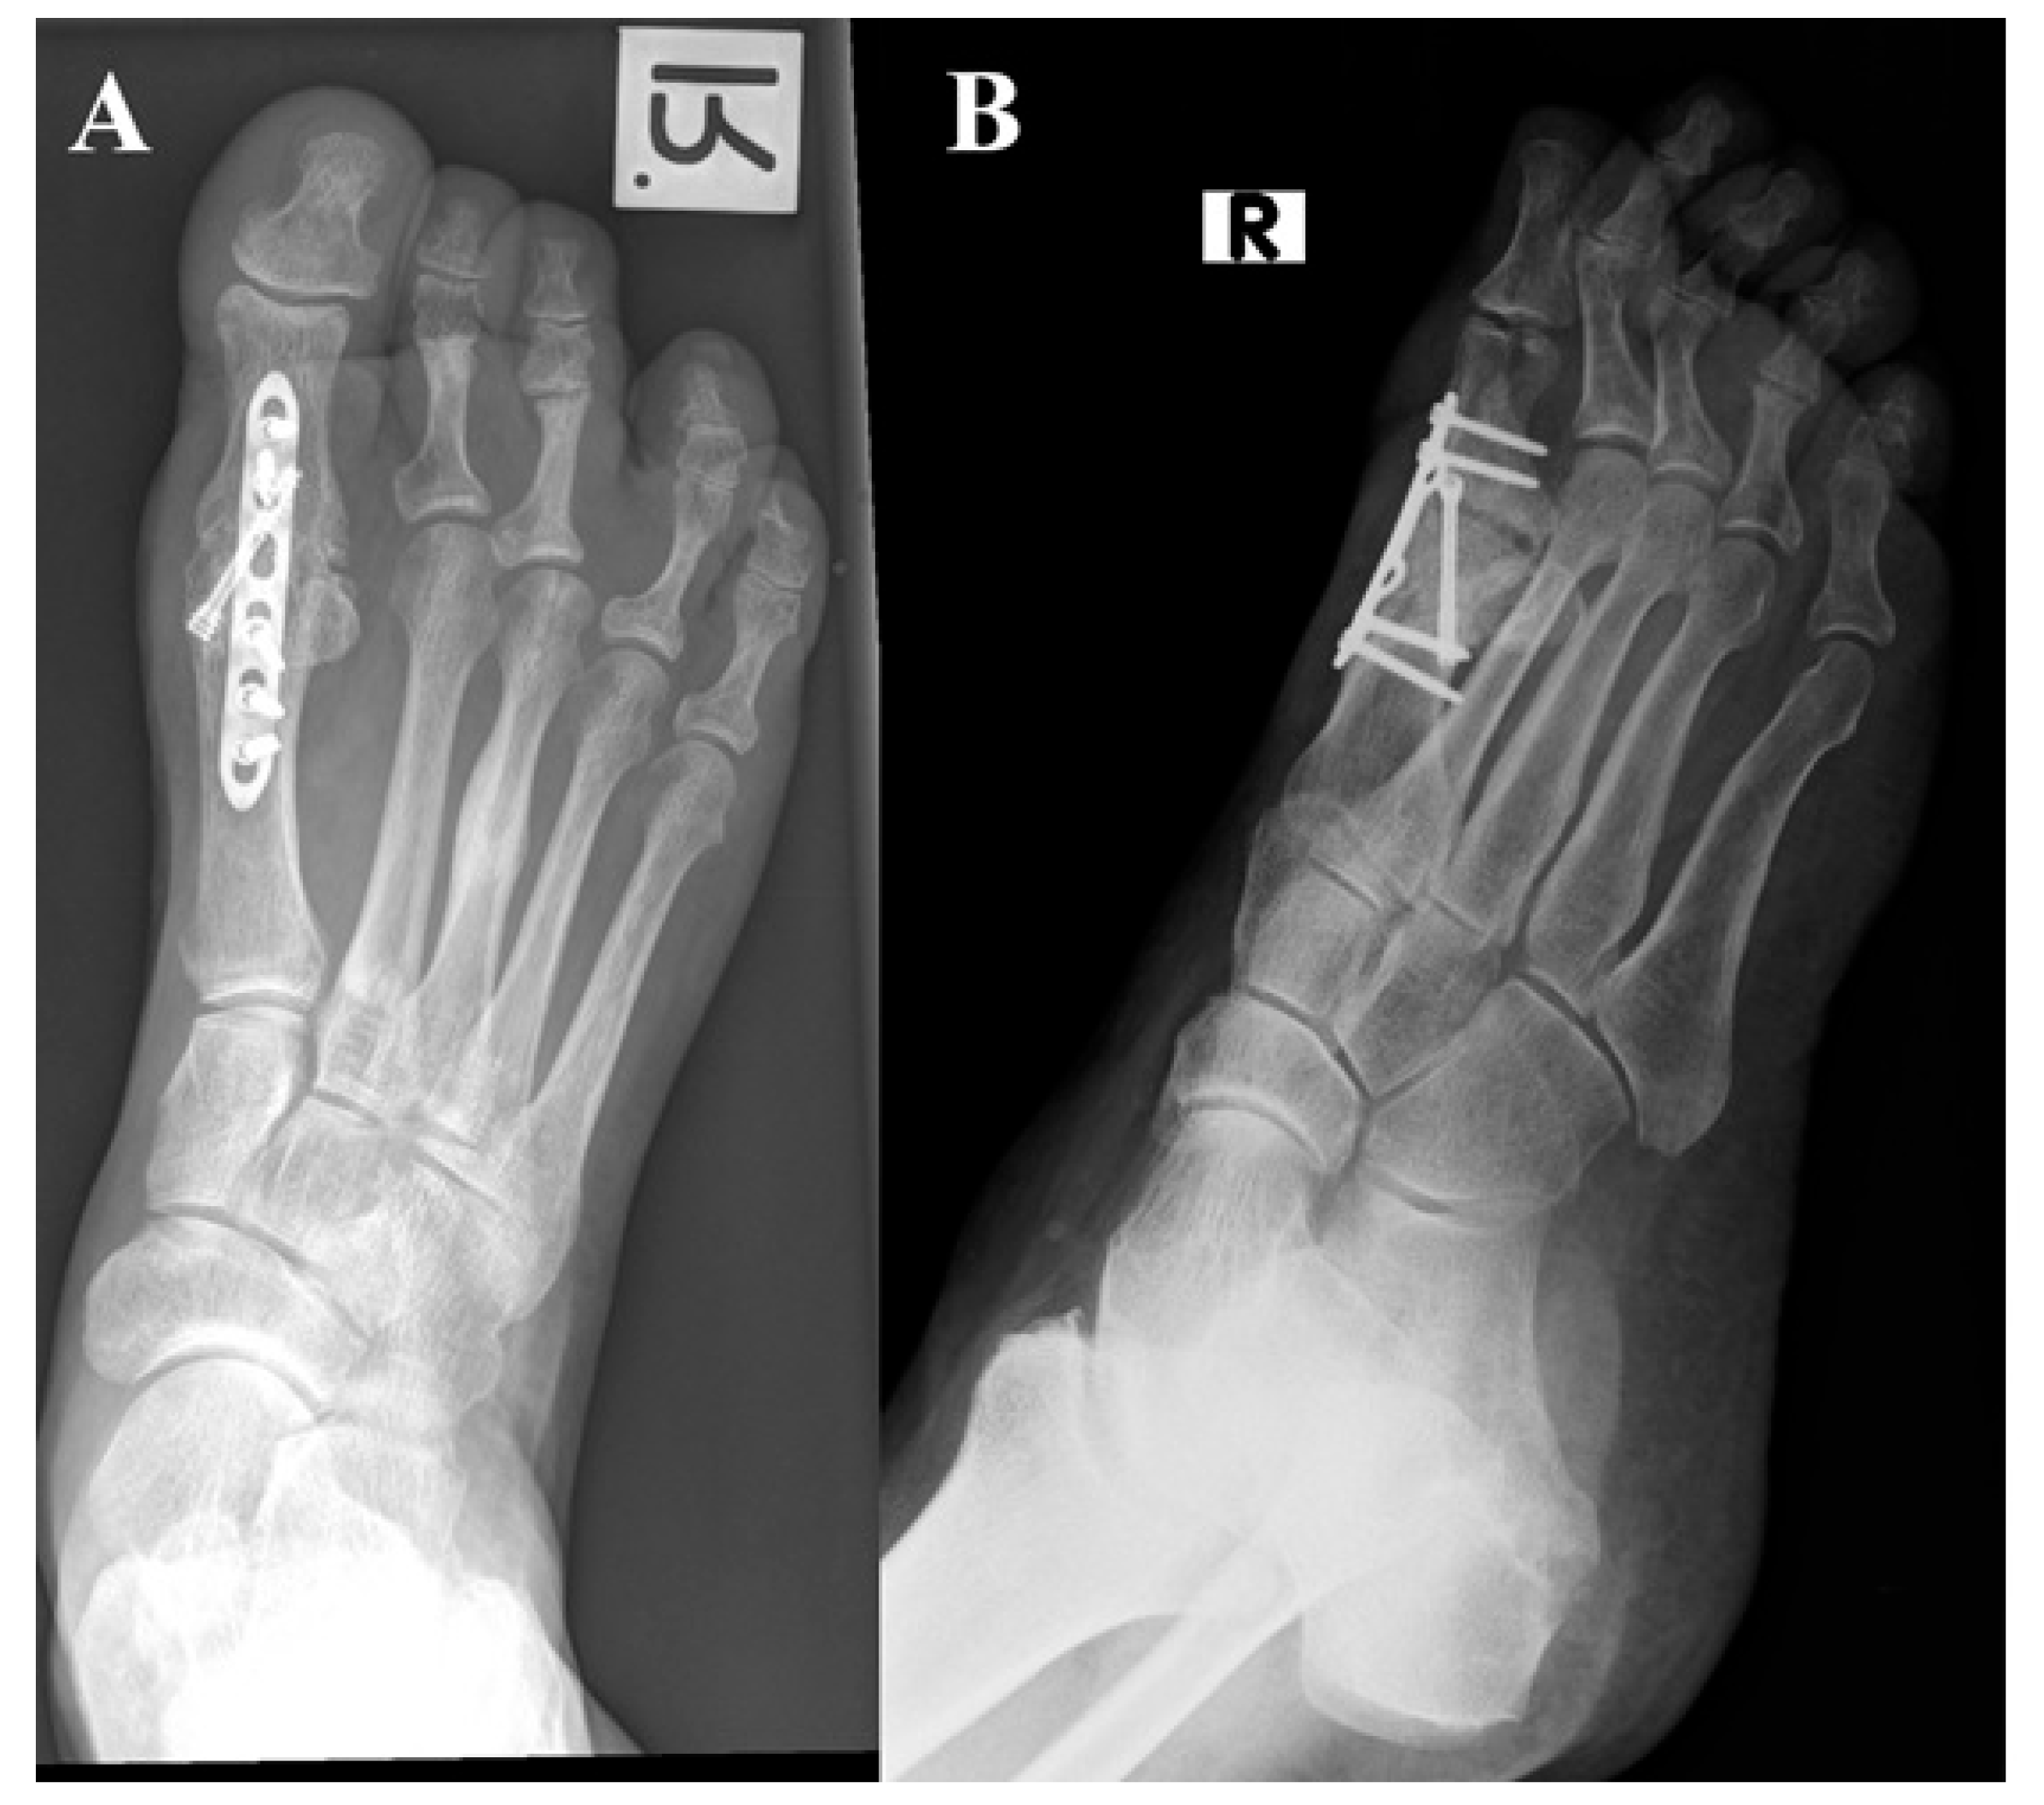

The primary outcome of this study focused on the occurrence of non-union at the fusion site. Non-union was assessed by the treating surgeon in the outpatient clinic, considering both clinical and radiographic findings (as illustrated in Figure 1). Clinically, non-union was defined as movement in the first metatarsophalangeal joint (MTPJ) with or without associated pain. Radiologically, non-union was characterized by the absence of bone bridging, as well as the presence of osteolysis, hardware migration, and lucency, all of which were evaluated at the 9-month post-surgery mark. To ensure accuracy, all radiographs were thoroughly re-evaluated by the senior authors to confirm the presence of non-union. Secondary outcomes of this study encompassed other complications that may have arisen and the occurrence of revision surgeries.

Figure 1.

Post-operative radiographs of patients with first MTPJ arthrodesis. (A) Complete first MTPJ fusion. (B) MTPJ non-union at 7 months after index procedure. MTPJ, metatarsophalangeal joint.